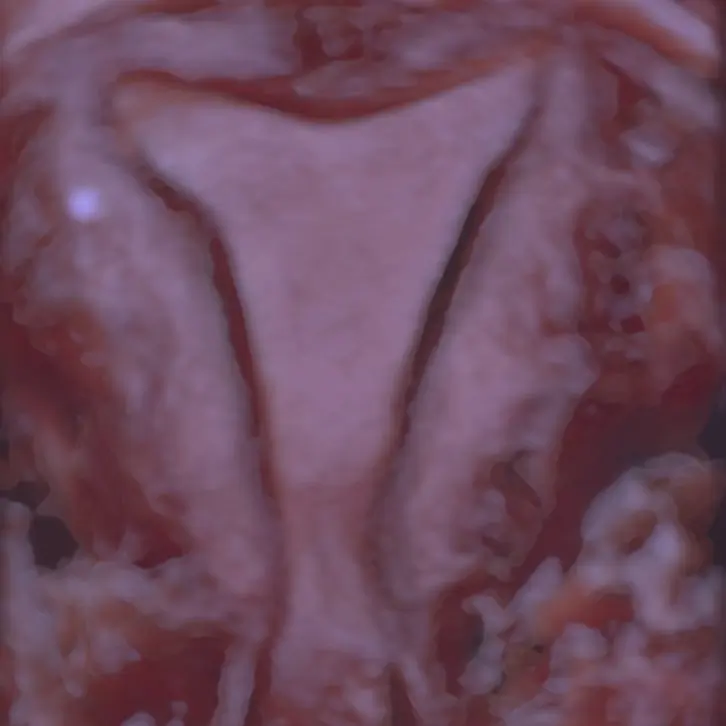

Per lo studio dell’anatomia pelvica femminile dall’età prepubere a quella post menopausale.

Tecnica ecografica finalizzata allo studio della cavità uterina e della pervietà tubarica senza l’utilizzo di radiazioni nè mezzi di contrasto.